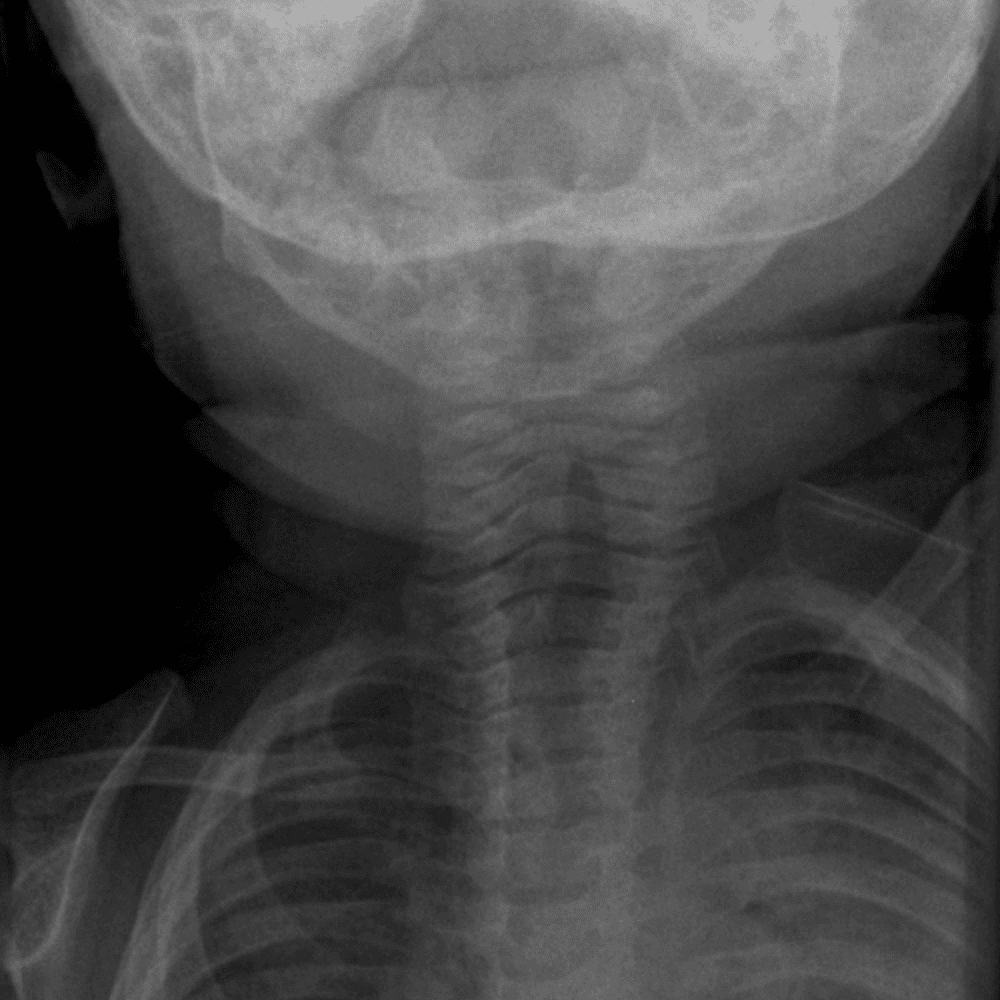

Peds Chest

Practice

Simulates call by including subtle or difficult cases and some normals.

50 cases